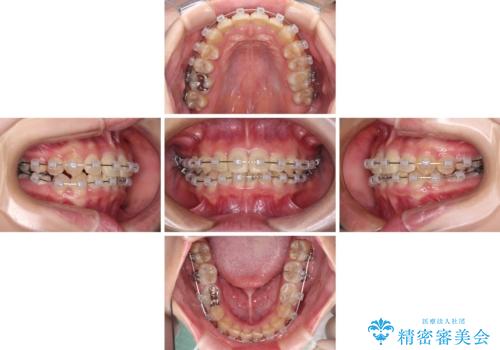

楽してクロスバイトを治したい ワイヤー装置による矯正治療

- 犬歯のクロスバイトを気にして来院された患者様です。

マウスピース矯正とワイヤー矯正の両方を提案しましたが、インビザラインの自己管理が煩わしいとのことで、ワイヤー装置による矯正治療を行うこととしました。

犬歯は歯根が太くて長いため、クロスバイトを改善するのは大変であることが多いですが、比較的スムーズに改善することができました。

インビザラインであったら、もっと期間はかかっていたような印象です。